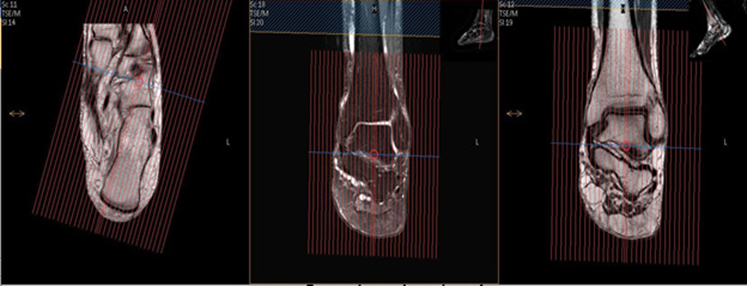

Angle to Tib/Fib (Ankle Protocol)

| AXIAL | T1 | TSE | 3mm | 0.3mm | None | 15cm | Cover thru Metatarsal Bases (as below) |

| AXIAL | T2 SPAIR | TSE | 3mm | 0.3mm | SPAIR | 15cm | Cover through metatarsal bases |

| SAG | T2 STIR | TSE | 3mm | 0.3mm | STIR | 15cm | Angle to Calcaneus |

| SAG | T1 | TSE | 3mm | 0.3mm | None | 15cm | Angle to Calcaneus |

| COR | T1 | TSE | 3mm | 0.3mm | None | 15cm | Perpendicular to Axial |

| COR | T2 SPAIR (run as STIR for infection) | TSE | 3mm | 0.3mm | SPAIR (or STIR) | 15cm | Perpendicular to Axial |